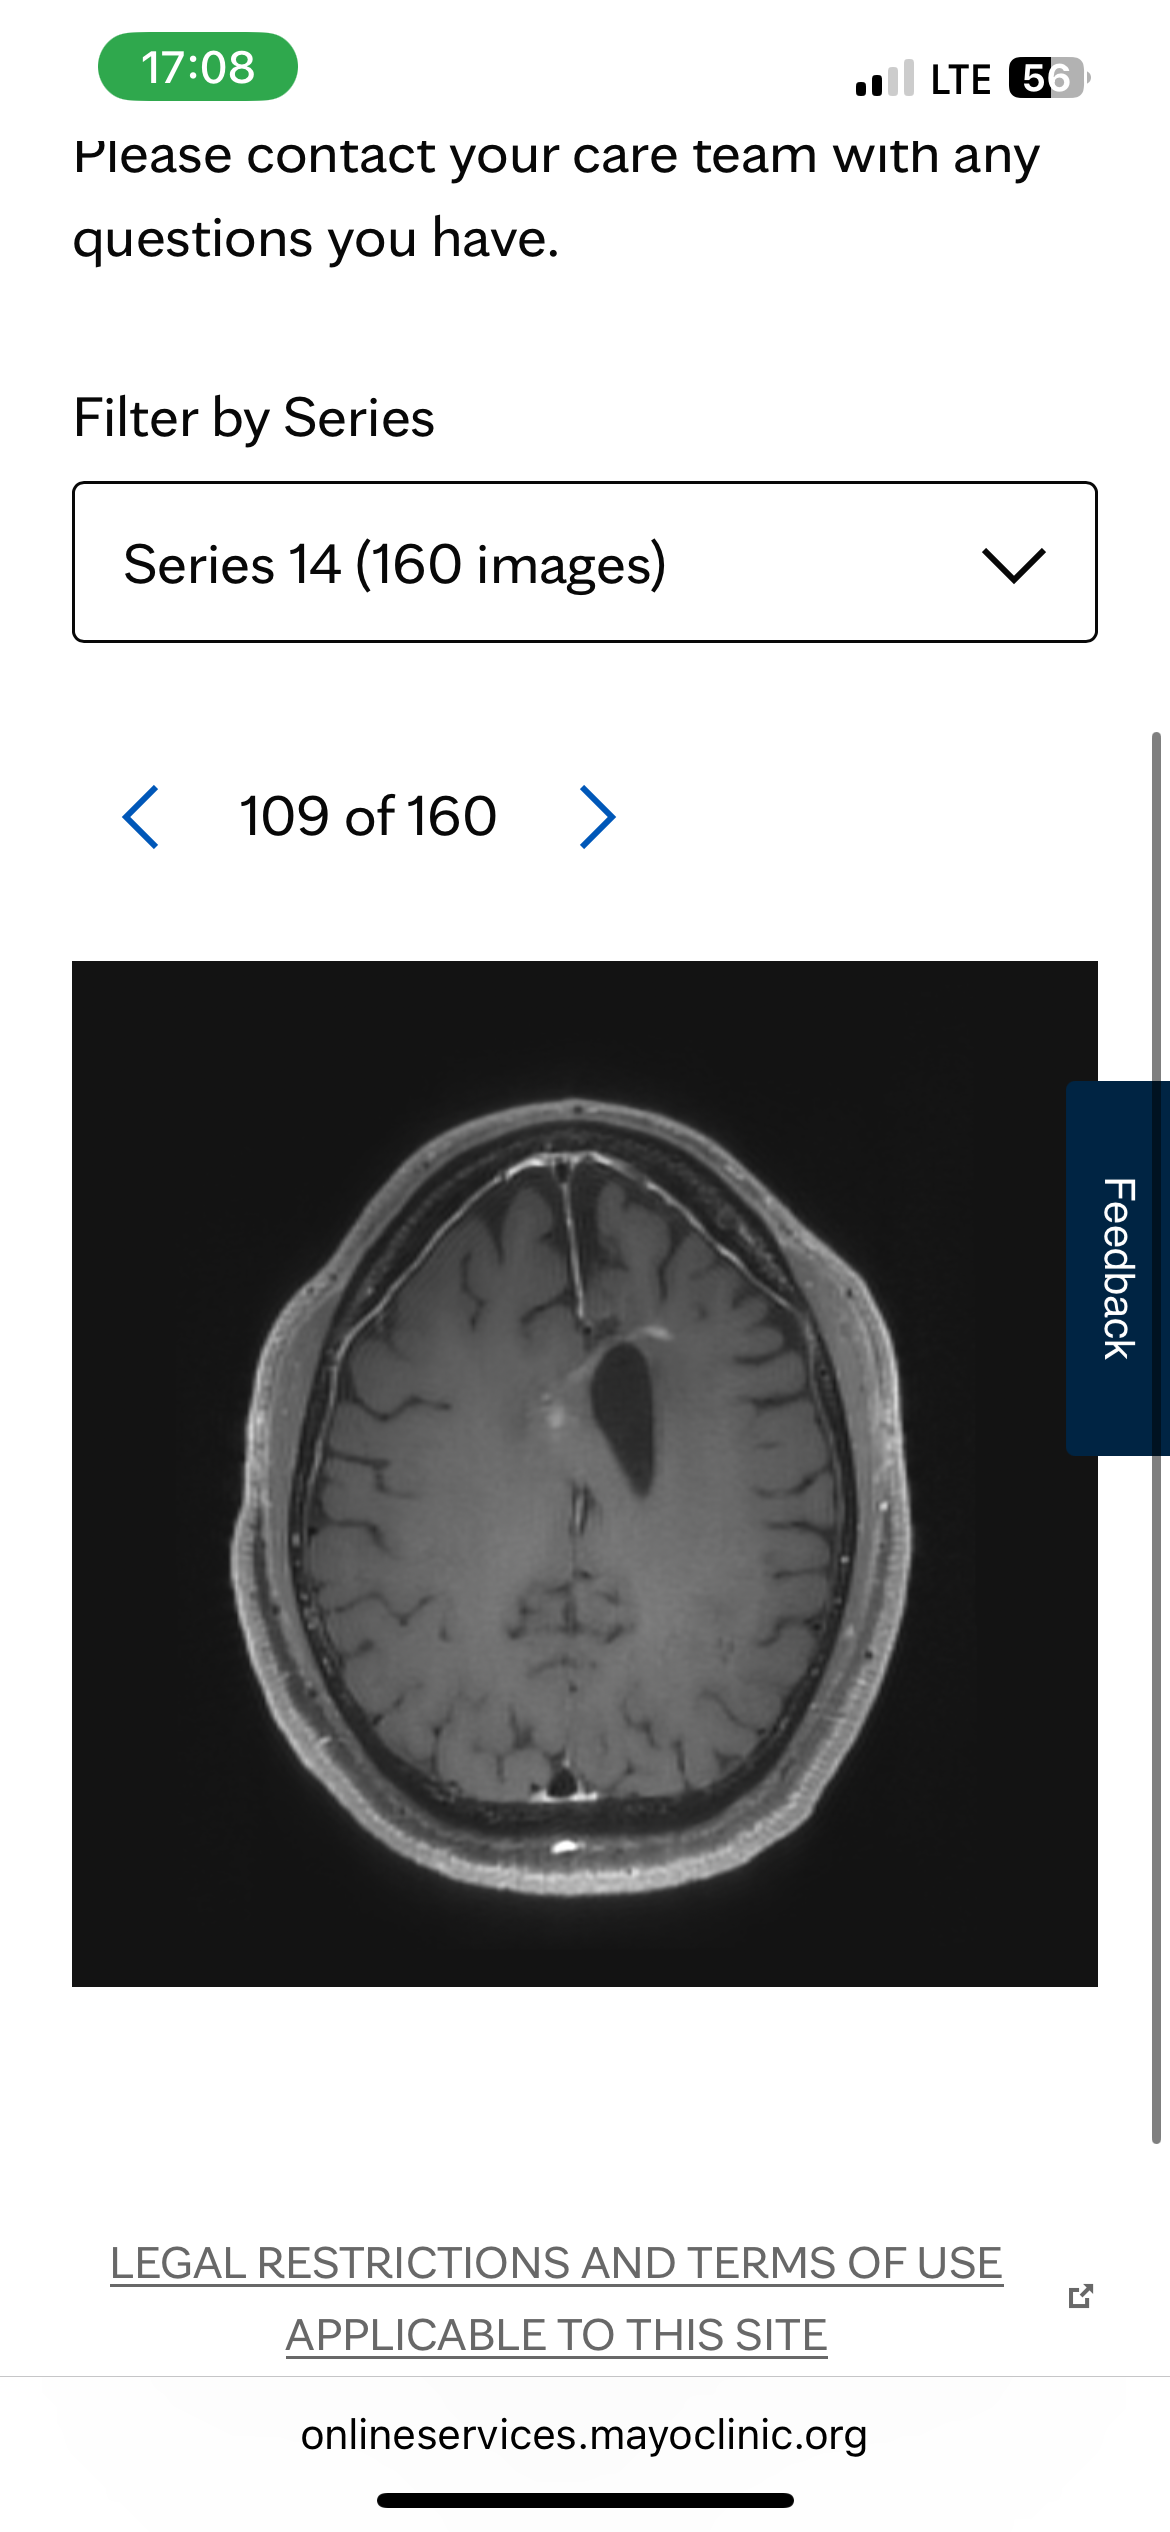

My husband has glioblastoma. Sadly, ten months into his battle, he has a recurrence. It is not operable, and he will begin another chemo. This chemo is usually not successful with his unmethylation type of GBM. He is already starting to have seizure auras and headaches. He wants to travel to Washington state to see our son and his new baby, wants to travel to Florida to see family, he wants to go to the Creation Museum, to the Grand Canyon, White Sands, and Washington DC.